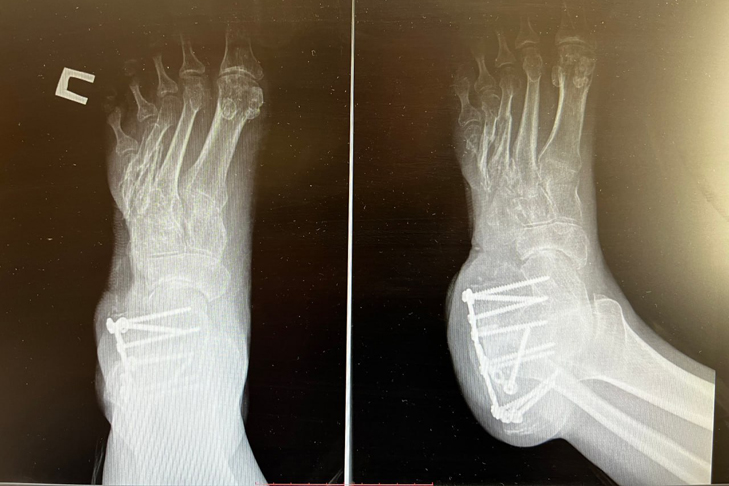

В течение пяти часов над пациентом одновременно работали травматологи и пластический хирург. Травматолог забрал фрагмент тазовой кости для её последующей пересадки в область стопы, потребовался трансплантат внушительных размеров: выпиленный фрагмент достигал 6,5 сантиметра в длину, 1,5 сантиметра в ширину и 1 сантиметра в толщину. Прежде чем имплантировать, хирурги подточили его точно по нужной форме.

На завершающем этапе травматолог-ортопед закрыл рану кожным лоскутом, который переместил с голени пациента. Причём лоскут был перенесён вместе с питающими его кровеносными сосудами — это ключевой момент, позволяющий коже прижиться на новом месте гораздо быстрее и надёжнее.